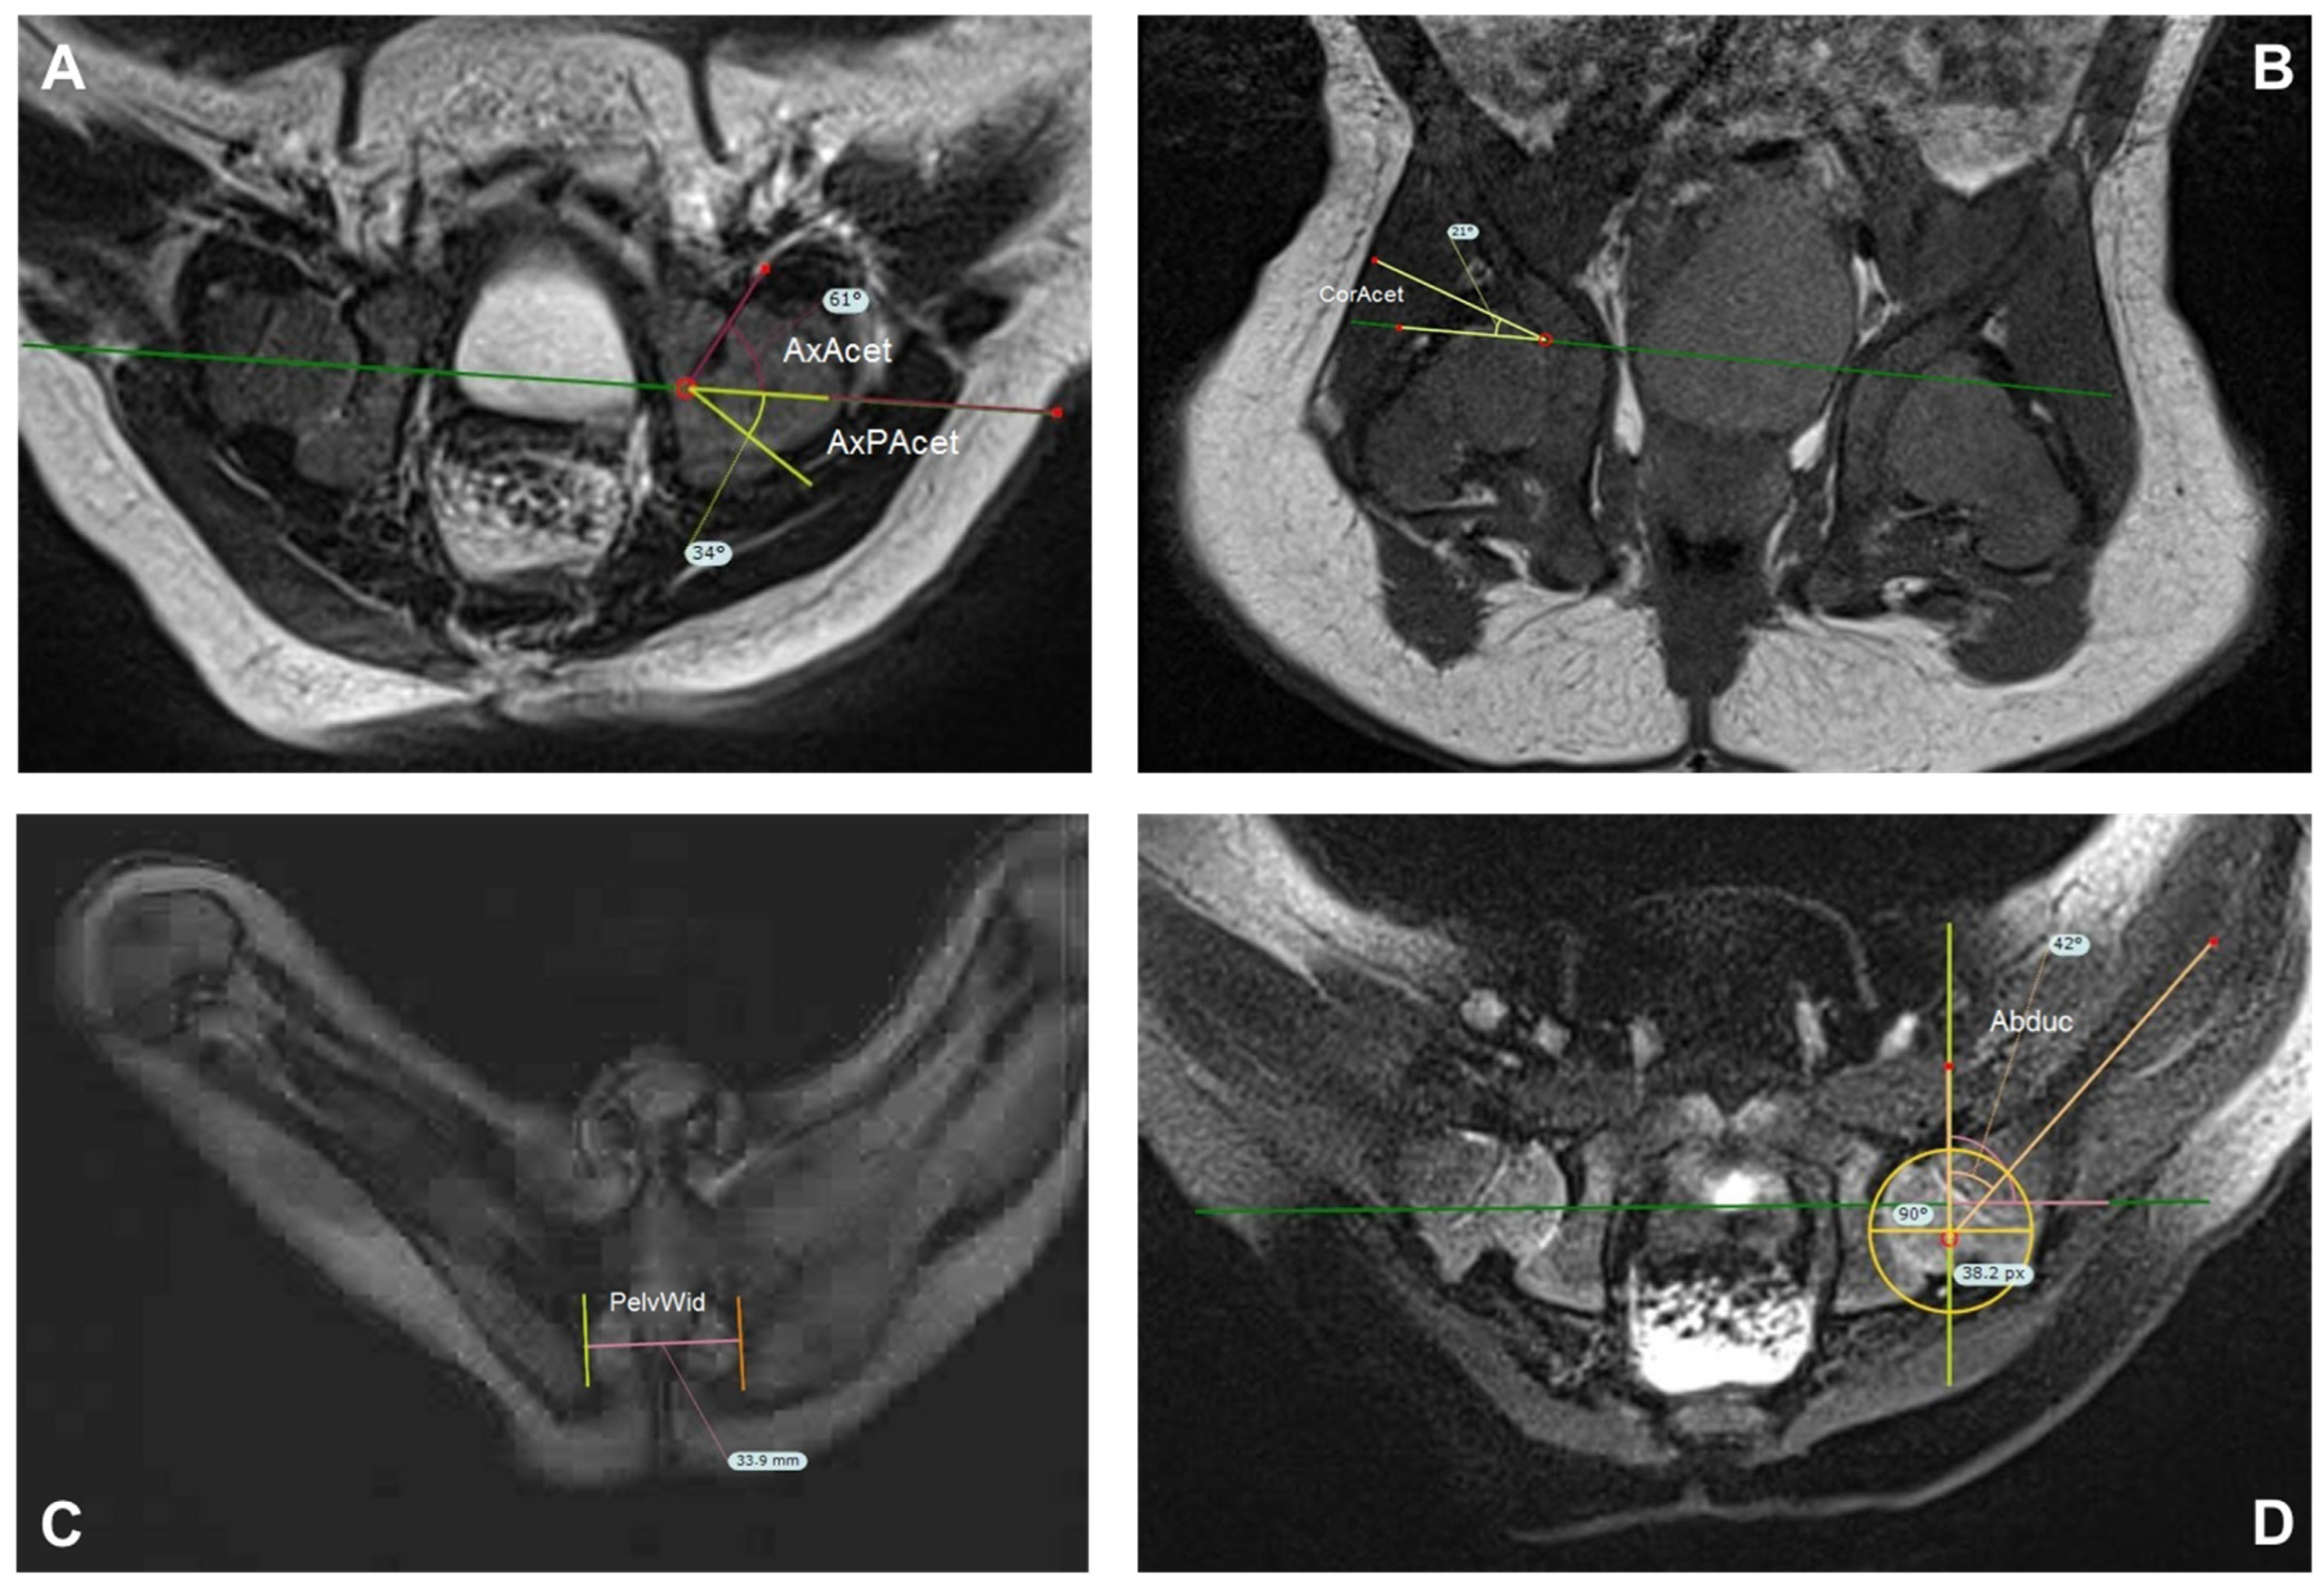

3.2. Magnetic Resonance Imaging Measurements

| Abd | 53.5 (39.3–66.2) | 5.2 | 53.4 (29.0–62.1) | 6.7 |

| AxAcet | 49.6 (32.8–68.2) | 7.1 | 50.0 (32.8–62.4) | 6.6 |

| AxPAcet | 46.8 (36.1–63.5) | 6.0 | 46.8 (4.6–69.1) | 9.3 |

| CorAcet | 25.6 (11.8–44.9) | 6.6 | 24.2 (11.7–47.6) | 7.8 |

| PelvWid | 35.8 (28.7–51.0) | 5.0 | 38.2 (32.0–52.0) | 5.1 |